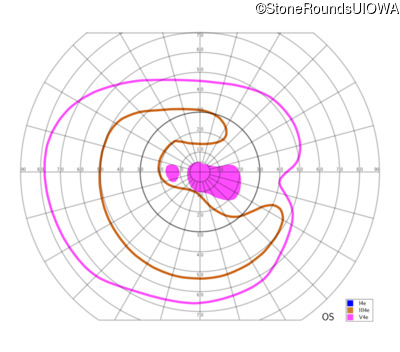

This 81 year old man began using a flashlight to read menus in his 40's. At age 75 his ophthalmologist noticed abnormal fundus findings and referred him to a retina specialist.

| Age at visit: 81 years |

| Age at visit: 82 years |

| Age at visit: 83 years |

| Age at visit: 84 years |

| Age at visit: 85+ (Visit 1) |

| Age at visit: 85+ (Visit 2) |

| OD | OS | ||

|---|---|---|---|